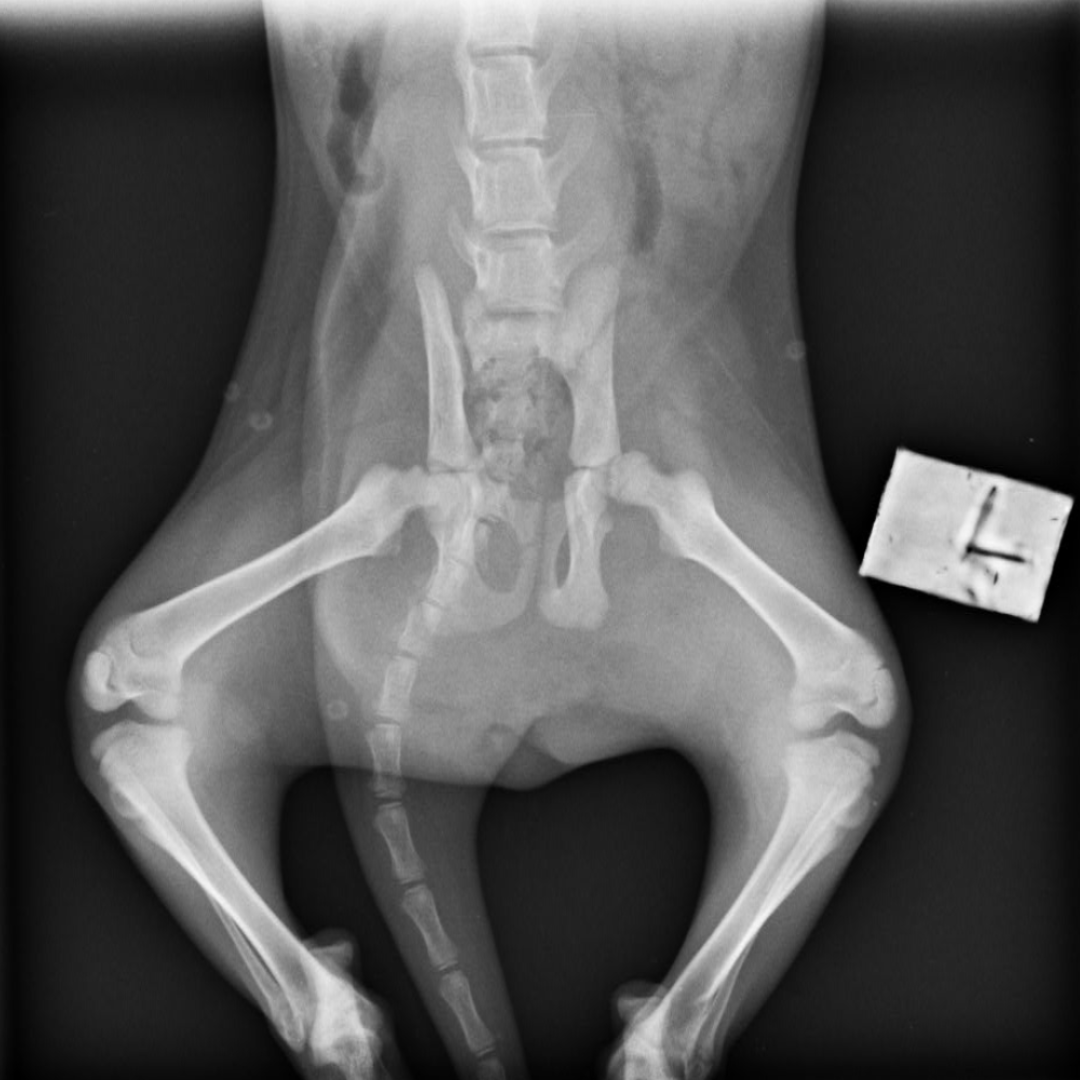

A few weeks ago, we were contacted by our partner vet in Limerick about a small 3-month-old kitten who was found in a ditch and had difficulty walking. ‘Blessing’ was the sweetest little thing, so full of love and purrs but also in some pain. Her x-rays showed that she had a double hip fracture which was mostly likely caused by being hit by a car.